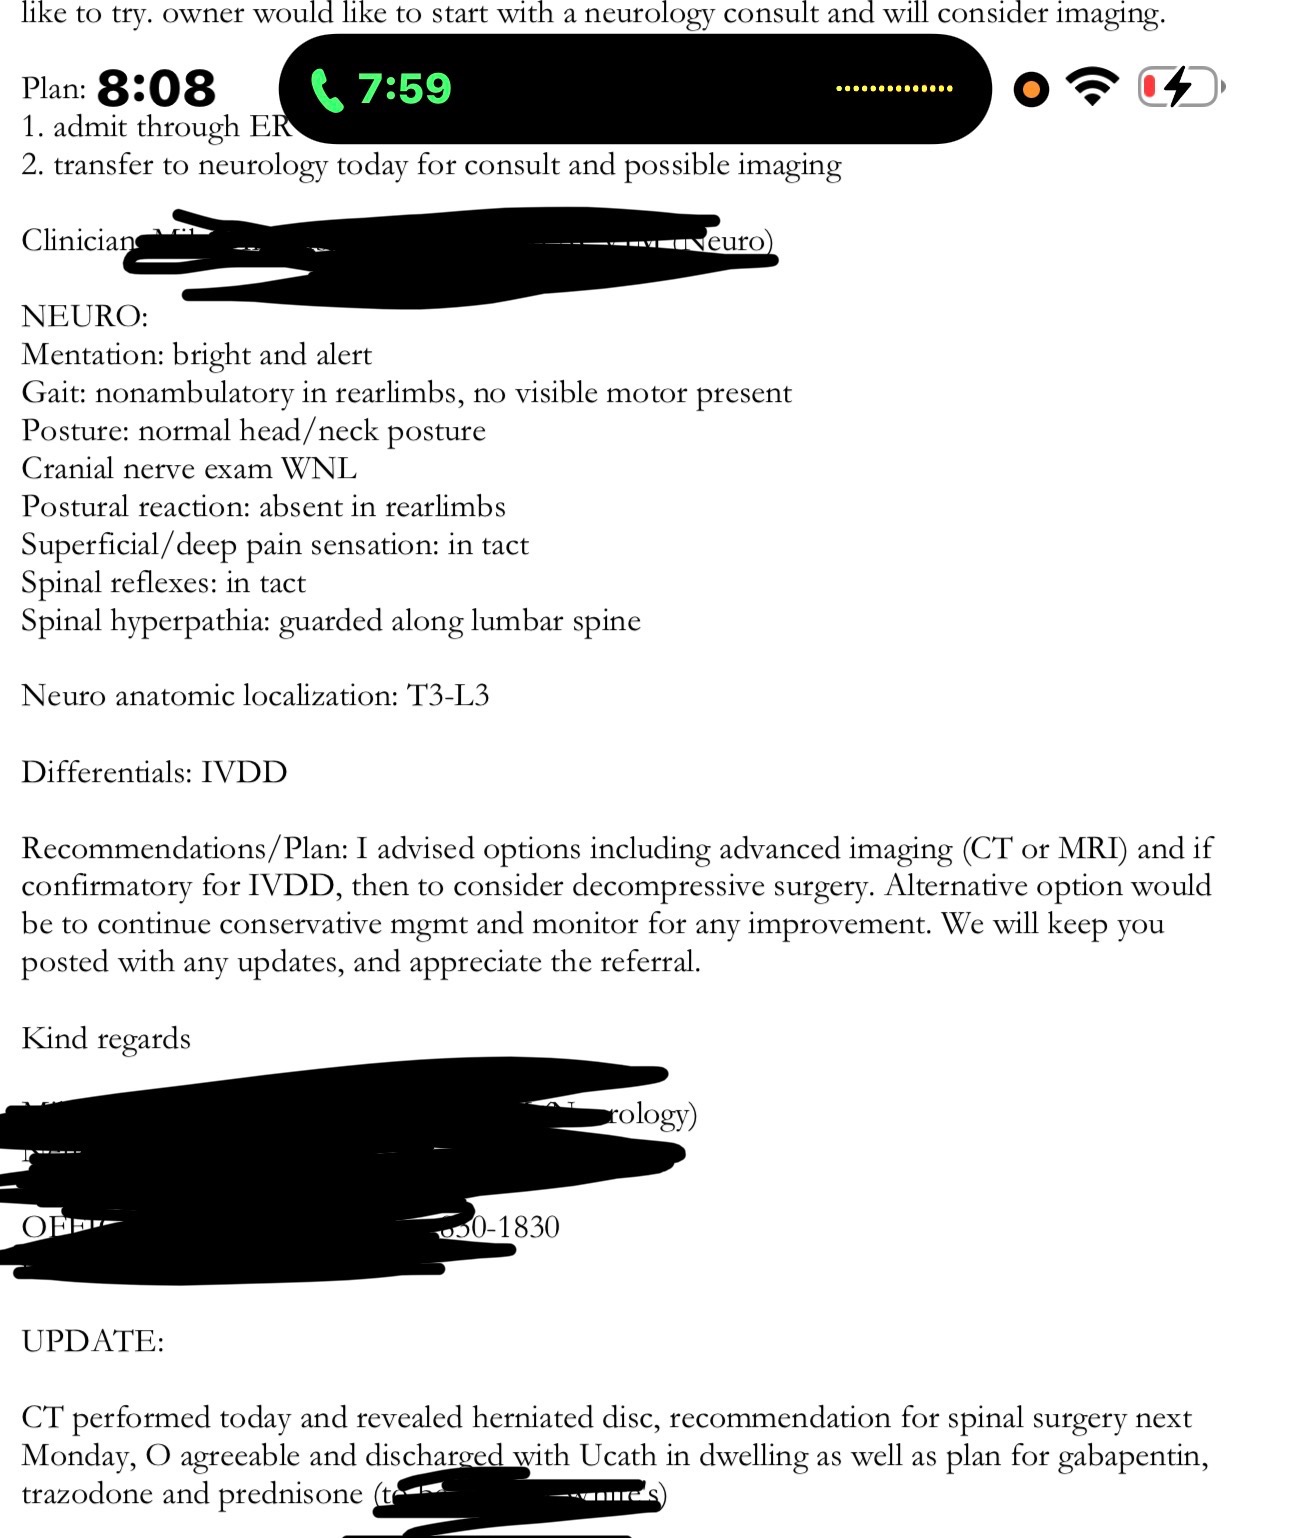

After multiple emergency veterinary visits, lab work, radiographs, CT imaging, and a neurology consultation at Veterinary Medical & Surgical Group (VMSG), Chompers was diagnosed with severe intervertebral disc disease (IVDD) with a confirmed herniated disc compressing his spinal cord.

This compression is causing:

• Paralysis of his hind legs

• Significant spinal and neck pain

• Loss of normal bladder function

The neurologist has strongly recommended urgent decompressive spinal surgery (hemilaminectomy) to relieve the pressure on his spinal cord and give him the best chance at recovery.